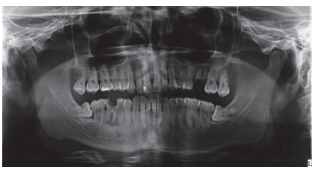

En la Historia Clínica no se evidenciaron antecedentes médico-quirúrgicos de interés, alergias medicamentosas conocidas ni hábitos nocivos. En la exploración extraoral no se apreciaron datos relevantes. En la exploración intraoral se apreciaron dientes no restaurables en posición de 2.6 y 4.6 y la presencia de los terceros molares inferiores retenidos. (Figuras 1 y 2).

En la exploración radiográfica, mediante radiografía panorámica, se apreciaron ambos terceros molares inferiores retenidos, en posición horizontal (Figura 3), e imágenes radiolúcidas apicales en posición de 2.6 y 4.6. En el escáner de haz cónico se evaluó la morfología radicular del tercer molar superior izquierdo, y la dimensión de la lesión radiolúcida apical del primer molar superior izquierdo (Figura 4), datos necesarios para valorar el grado de adaptación del diente donante en el lecho receptor.